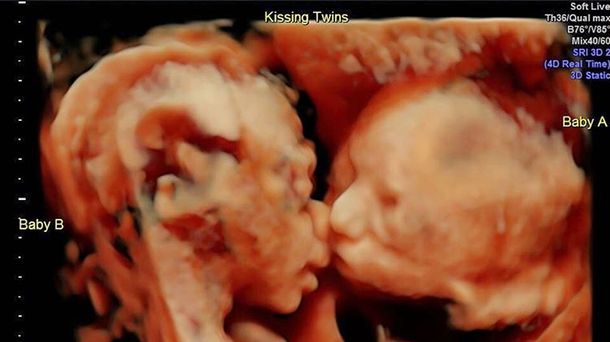

Isabella y Callie en la imagen más tierna

Es que la mujer compartió una inédita ecografía donde se va a sus gemelas de 25 semanas besándose y abrazándose y la imagen desborda de ternura.

"Isabella dándole a su hermanita Callie un beso en la mejilla", escribió. "Estoy sobrepasada por el amor y el apoyo que he recibido por estos dos preciosos bebés y el ultrasonido que compartí con todos vosotros. Estoy de 25 semanas y ansiosa y emocionada por conocer a mis niñas", agregó la mujer.